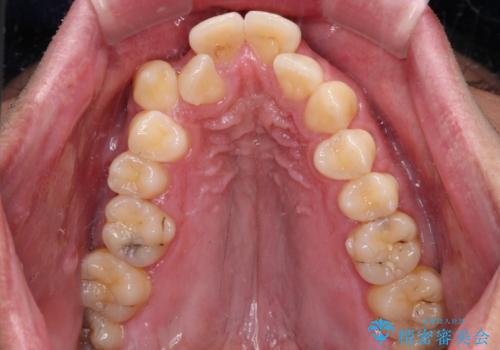

- デコボコと前歯の突出感を気にして来院された患者様です。

舌の突出癖などにより上顎前歯が前方に突出し、さらに歯列幅が狭小になっている状態でした。

また、上顎歯列全体が下顎に対して前方位に位置していました。

上顎歯列幅を側方に拡大するとともに、歯列全体を後方に移動させるためのアンカースクリューと補助装置を使用し、上顎左右第一小臼歯2本、下顎左右第二小臼歯2本、計4本を抜歯し、ワイヤー装置にて矯正治療を行うこととしました。